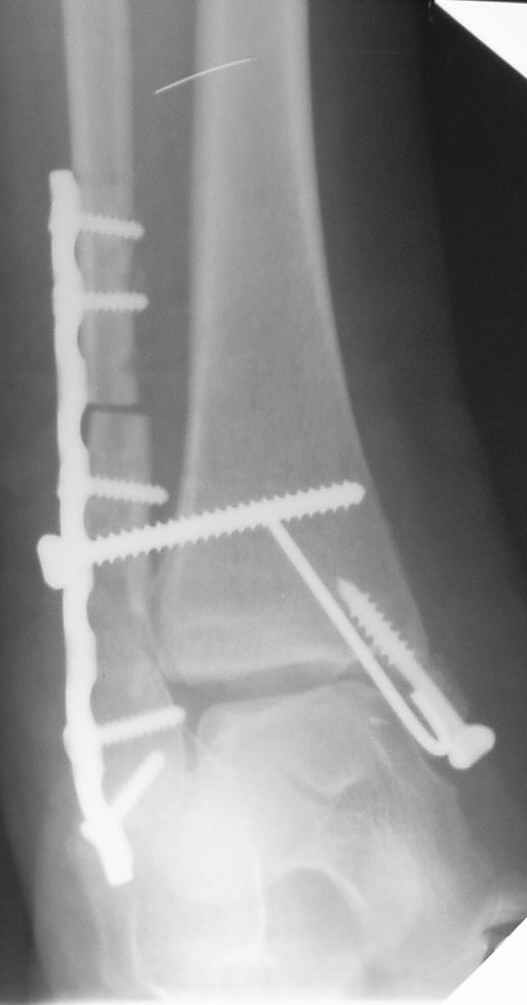

Уважаемые коллеги! Персонально, дорогой доктор Джолдас. Не знаю, почему почта к тебе не проходит - у меня почтовая программа "Bat", снимки в JPG. Выставляю через форум. 10 апреля я показывал снимки больной с застарелым переломо-вывихом голеностопного сустава. 9 июня прооперировал, снимки прилагаю. R-контроль через месяц ходьбы на костылях, все стоит также. Разрешил частичную (20кг) нагрузку на ногу, пока жалоб нет.

Ход операции - сагиттальная остеотомия по линии неправильно сросшегося перелома малоберцовой кости, остеотомия с формированием внутренней лодыжки, попытка вправления подвывиха неудачна из-за того, что "не хватало" длины малоберцовой. Остеотомия малоберцовой кости выше синдесмоза. Остеосинтез.